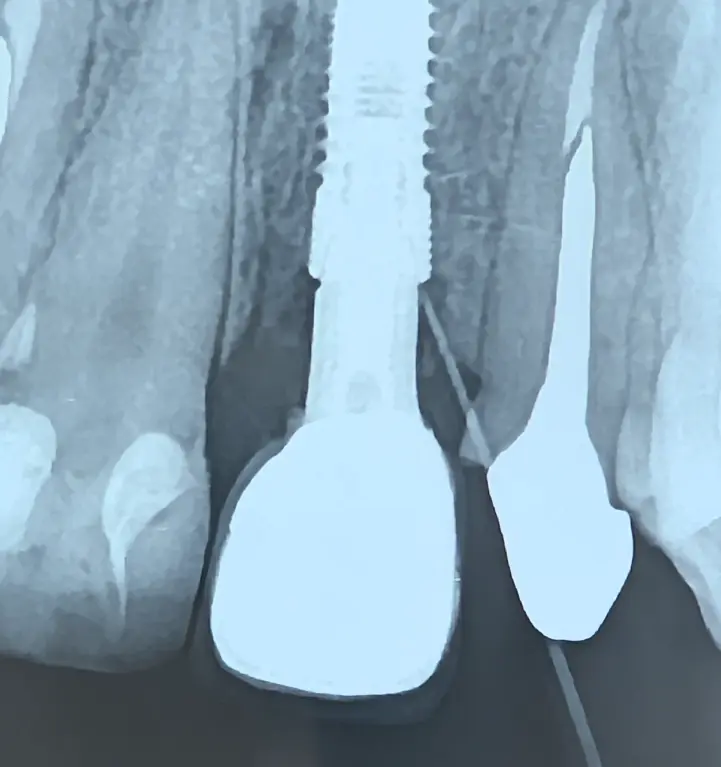

نمای تریس آبسه و ارتباط آن با کانکشن ایمپلنت

در نهایت، با تریس مسیر آبسه مشخص شد که منشأ آبسه کانکشن ایمپلنت است؛ نه استخوان و نه فیکسچر. بنابراین نیازی به خارج‌سازی ایمپلنت نبود.

نمای داخل کانکشن ایمپلنت و سمان باقیمانده

پس از خارج‌کردن روکش مشخص شد:

سمان باقیمانده در داخل کانکشن، عامل التهاب مزمن و آبسه بوده است.